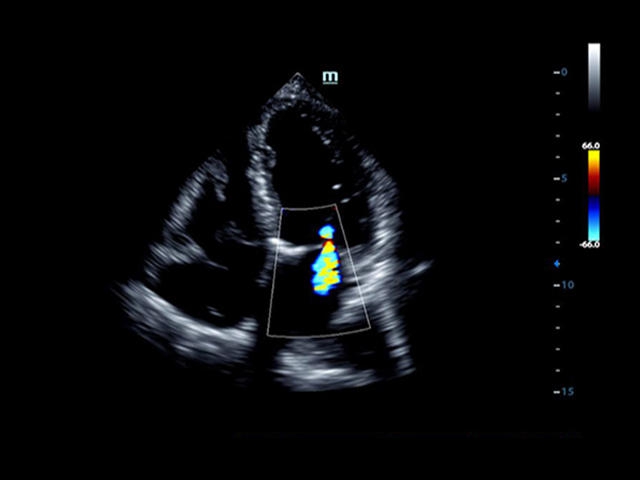

• LVO - опция проведения исследования левого желудочка сердца с применением контрастных веществ;

• LVO - опция проведения исследования левого желудочка с применением контрастных веществ